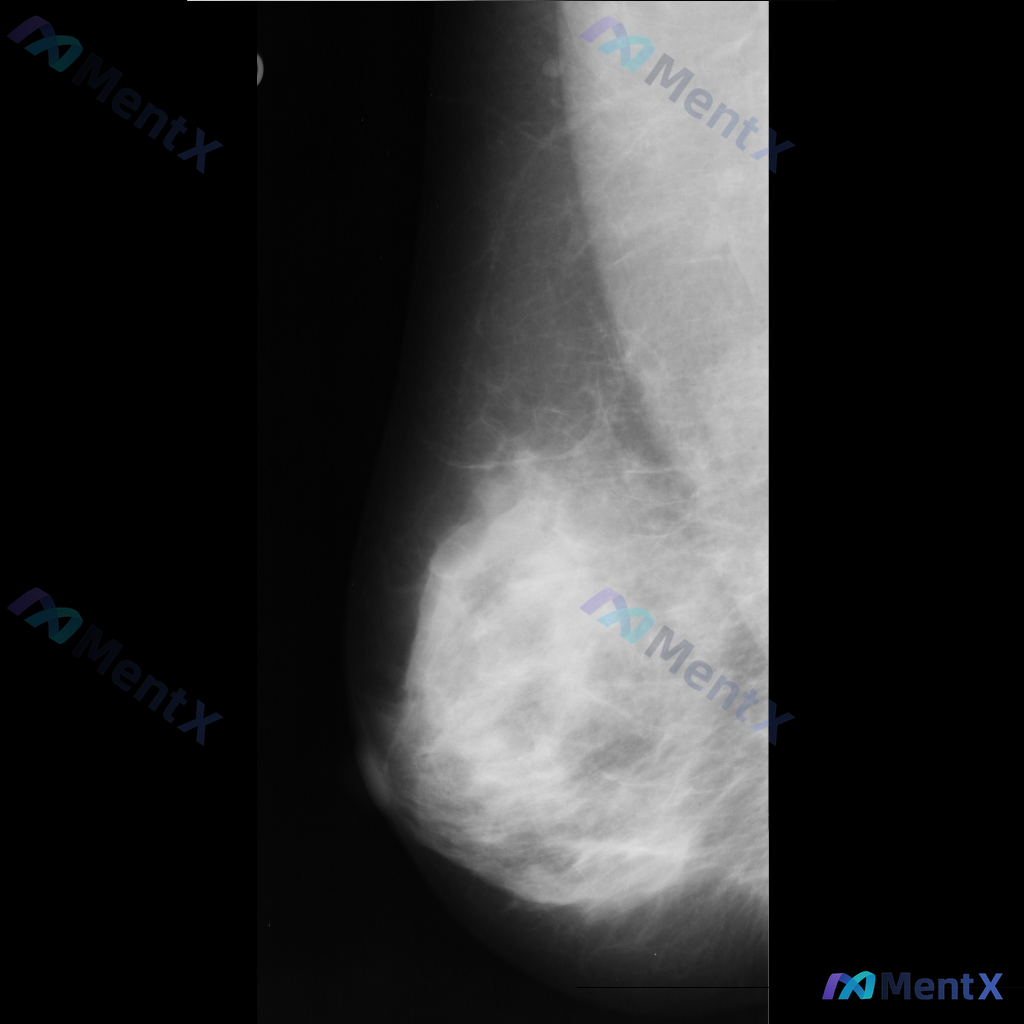

整理到一份乳腺钼靶的影像资料,想和大家讨论一下: - 钼靶所见:左侧乳腺中央偏下区域存在局限性结构扭曲,表现为纤维腺体组织排列紊乱、牵拉;未见明确的肿块或钙化灶。 - 背景:乳腺密度较高,属于不均匀致密型或极度致密型(ACR B或C型)。 目前这种结构扭曲的表现,大家会先往哪个方向考虑?下一步的评估...